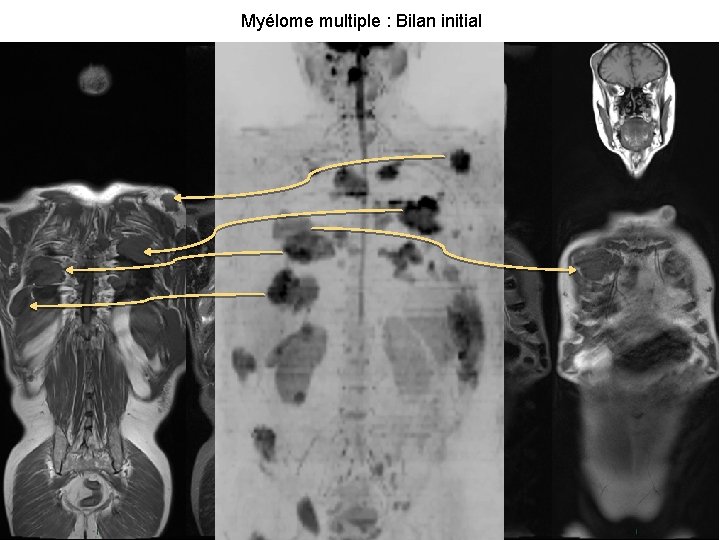

Myélome multiple : Bilan initial 15

Retrouver les anomalies détectées Myélome multiple T 1 Diffusion + 16 Fusion =

Rôle de la diffusion dans l’interprétation Détecter les lésions grâce aux images « fonctionnelles » Facilite la détection des lésions(1) 43% tumeurs supplémentaires détectées grâce à la diffusion 6, 5% visibles uniquement sur les séquences DWI 1, 8% tumeurs bénignes Localiser les images à l’aide de la fusion 17 Améliore la sensibilité et la spécificité(2) Fusion (diffusion + T 1) Diffusion et T 1 Sensibilité 90% 72% Spécificité 82% 59% 1. Low RN. JMRI 2007 2. Tsushima Y. Acad Radiol. 2007